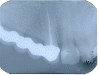

Devitalizzazione